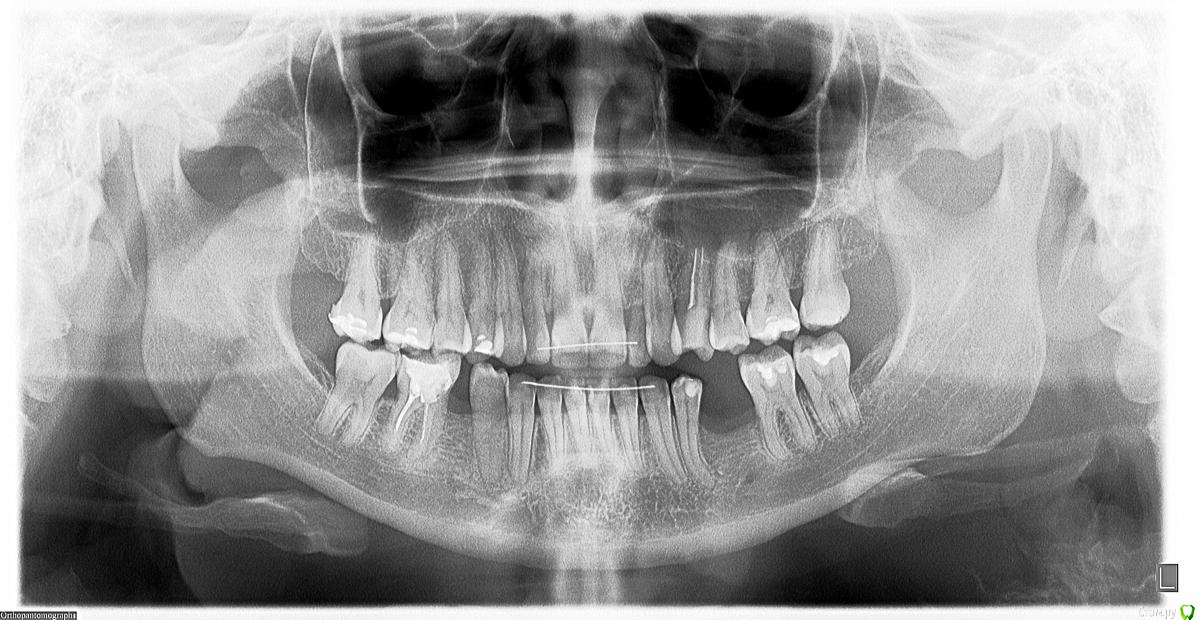

Девушка_пациентка Опубликовано 19 февраля, 2015 Поделиться Опубликовано 19 февраля, 2015 Добрый день, уважаемые профессионалы!У меня довольно сложный случай, как мне говорят. Хотелось бы услышать ваши комментарии и советы по поводу стратегии лечения/протезирования.Мне 36 лет. На нижней челюсти есть отсутствующие зубы. Дело в том, что их и не было никогда. Я не помню, чтобы мне когда-либо что-либо удаляли. Позабыть этого факта я бы не могла. Судя по смнимку стоматологи в нашем городе, у кого я была на консультации, утверждают, что состояние моей костной ткани - на 50-летний возраст. При этом у меня нет воспалительного процесса и кровоточивости десен. (Ретейнеры стоят из-за ортодонтического лечения, которое я проходила в 2010-2011 годах, исправляли клык на верхней челюсти). Тем не менее, десна у коренных зубов оседает, оголяя все больше их корни. Вопрос о мостах не стоит, т.к. опорные зубы не выдержат скорее всего такой нагрузки. Что касается имплантации, то в сентябре 2014 года мне была выполнена подсадка костной ткани внизу слева. Полгода я пила припараты кальция: Остеогеноно и Остеокомплекс. На контрольном снимке через 6 мес. (на мой дилетантский взгляд) ситуация стала выглядет еще хуже... Врач порекомендовал мне пить кальций еще как минимум год. А пока поменять пломбы в нижних зубах и один из них (с сильно оголившимся корнем) депульпировать.У меня ложилось впечатление, что он просто "умыл руки" и отправил меня по добру по здорову. Видимо, случай действительно сложный и он просто не хочет браться за него. А сказать об этом прямо почему-то не решился. Хотя, я могу ошибаться. Прошу ваших рекомендаций и прогноза.Показана ли имплантация в таких случаях, как мой? Каковы прогнозы? P.S. Диабетом, ревматизмом и пр. не страдаю. После родов в 2012 году было некоторое время нарушение кальциево-фосфорного обмена. Сейчас по анализам - норма. В анамнезе гопотериоз, но с 2008 года - стойкая ремиссия, не требующая приема препаратов. Гормоны с 2008 года контролирую каждые 3 месяца, - все в норме. В ближайшие полгода планирую вторую беременность. Хотелось бы только привести в порядок зубы перед этим. Стоит ли заниматься имплантацией сейчас или, в таком случае, целесообразнее отложить ее на более позднее время, а сейчас просто вылечить зубы (нижние коренные требуют замены пломб) и продолжать пить кальций? Прикрепляю снимки:1) Состояние на 04.09.2014 (перед подсадкой костной ткани слева с целью последующей имплантации)2) Состояние на февраль 2015 года (спустя 6 мес. после подсадки). Ссылка на комментарий